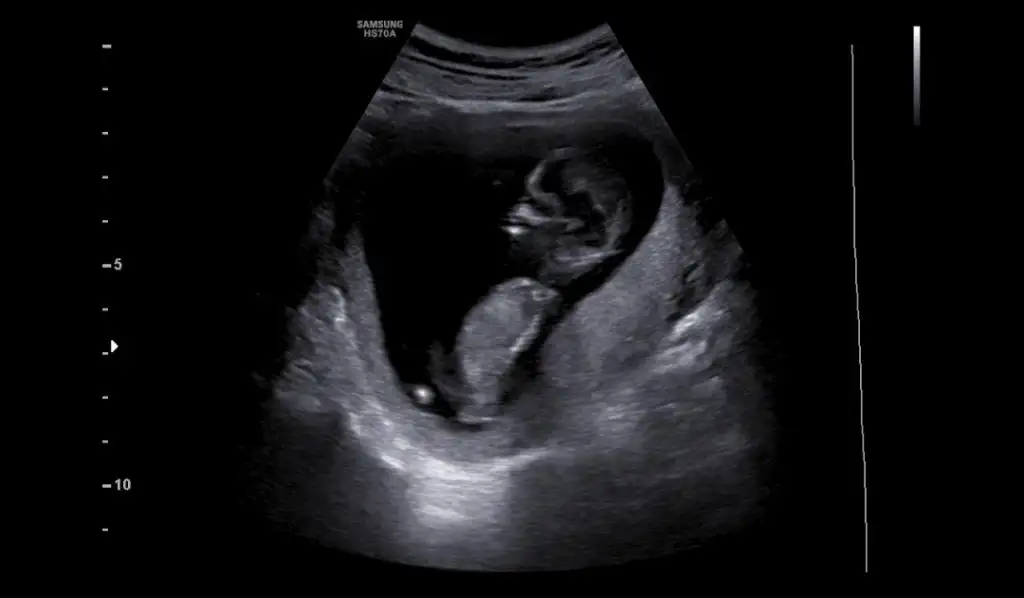

Merhaba bana da tahmin yapabilir misiniz?Erkek ve kız için 11 + 12+ yada 13 hafta usg görüntüsü olmalı açıklamalar asagıda yazıyorrabbim herkesin gönlüne göre nasip etsin inşallah .. ecmain

[/B]Eki Görüntüle 473828 gordugunuz gibi ust taraftaki simgedende anlasildigi gibi eger cikinti paralel ise kiz

yok 30°lik bir aciyla yukari dogru bakiyorsa %99 oglunuz olacak demektir simdi bi kac ornek resimler daha koyacagim kiziminkide dahil

Eki Görüntüle 473829 bu bir erkek bebek genital nub cikintisi gayet yukarda

Eki Görüntüle 473831 simdi burada cikintilara bakin eger bel popo cizgisine paralel ise kiz

yok 30 derecelik bir aciyla yukari bakiyorsa erkek

yabancilarin hepsi biliyor bunu biz neden eksik kalalim gayet bilimsel simdi ellerinde11 12 13 ultrason fotografi olanlar alsin hemen baksin yada koyalim buraya